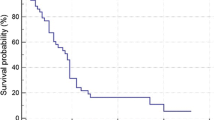

The population included for tumor volumetry had a mOS of 11 months (95% CI 8–14 months). In univariable Cox regression, age above 70 years and the presence of liver cirrhosis significantly decreased patient survival; prior ablation, cTACE, or systemic therapy were no significant predictors, nor was response according to qEASL criteria on follow-up MRI with a p value of 0.06 (Table 3). In multivariable Cox regression, survival was best explained by a model that included qEASL response, the status on cirrhosis, and patient age above or below 70 years as predictors (chi-squared test, p = 0.001), whereas qEASL response was the single strongest predictor with a HR of 2.6 (p = 0.03) (Table 3). Survival curves for the stratification into MRI morphologic responders and non-responders are shown in Fig. 5. Median survival in non-responders was 11 months (95% CI 8–14 months) and 17 months in responders (95% CI 13–21 months).

Comparison of survival times of MRI morphologic therapy responders and non-responders with Cox regression. Survival curves for the stratification into responders and non-responders who showed a reduction of enhancing tumor volume (ETV) greater or smaller than 65% in follow-up MRI. Median survival in non-responders was 11 months (95% confidence interval (CI) 8–14 months) and 17 months in responders (95% CI 13–21 months); the adjusted hazard ratio (HR) was 2.62. Numbers at risk and numbers censored are given at the beginning of the interval